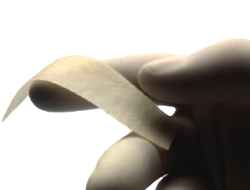

Las coaliciones tarsales son las uniones entre los huesos del tarso mediante puentes óseos (sinostosis), fibrosos (sindesmosis) o cartilaginosos (sincondrosis), completos o incompletos, que se producen como defecto de segmentación en el mesénquima primitivo (Figura 1). La incidencia de las coaliciones tarsales se estima menor del 1%, aunque algunos autores como Klammer(1) indican que puede llegar a un 6%. Pueden ser aisladas, unilaterales o bilaterales, o bien estar asociadas a otras malformaciones(2,3,4,5,6,7). La sinostosis calcaneoescafoidea tiene una prevalencia de alrededor del 50% y la talocalcánea del 40%(8). La distribución por sexos es equivalente.

Figura 1. Segundo caso: coalición tarsal talocalcánea sinostótica bilateral. Pie derecho. Tomografía axial computarizada y radiografía.